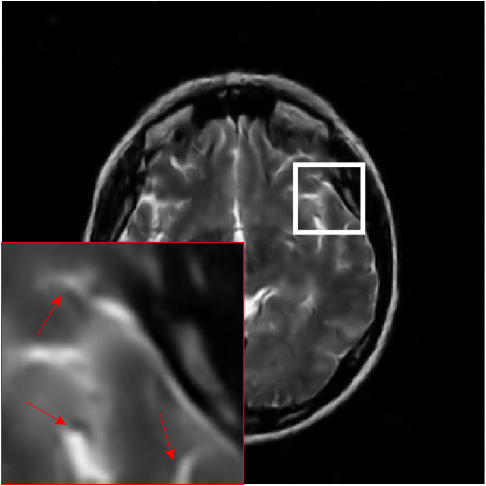

Where x is denoted as the MRI to be reconstructed, y are the k-space data, and Fusubscript𝐹𝑢{F_{u}} represents the under-sampled Fourier encoding matrix. The first term Fuxy22superscriptsubscriptnormsubscript𝐹𝑢xy22{\|{F_{u}}\emph{x}-\emph{y}\|}_{2}^{2} indicates data fidelity that can ensure the consistence between the Fourier coefficients of the reconstructed image and measured data. The second term Risubscript𝑅𝑖{R_{i}} is an analytical, sparsifying transform term, and αisubscript𝛼𝑖{\alpha_{i}} is a factor for balancing data fidelity and transform terms. MR images can be generated by inverse Fourier transform of the sampled k-space data, which are the Fourier coefficient of an object. However, aliasing artifacts (noise-like) are produced by the incoherence of under-sampled k-space in transform domain, as shown in Fig. 1.

Figure 1: The zero-filled reconstruction. (a) is a full-sampled MRI, (b) is a 20% radial sampling mask, (c) is the zero-filled reconstruction under (b), and (d) is the reconstruction using our method. Note that aliasing artifacts are clearly seen in the zero-filled reconstruction (c), which impair diagnostic information. However, our algorithm can remove these unpleasant artifacts (d).